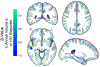

Growing evidence points to persistent neurological injury in chronic HIV infection. It remains unclear whether chronically HIV-infected individuals on combined antiretroviral therapy (cART) develop progressive brain injury and impaired neurocognitive function despite successful viral suppression and immunological restoration. In a longitudinal neuroimaging study for the HIV Neuroimaging Consortium (HIVNC), we used tensor-based morphometry to map the annual rate of change of regional brain volumes (mean time interval 1.0 ± 0.5 yrs), in 155 chronically infected and treated HIV+ participants (mean age 48.0 ± 8.9 years; 83.9% male) . We tested for associations between rates of brain tissue loss and clinical measures of infection severity (nadir or baseline CD4+ cell count and baseline HIV plasma RNA concentration), HIV duration, cART CNS penetration-effectiveness scores, age, as well as change in AIDS Dementia Complex stage. We found significant brain tissue loss across HIV+ participants, including those neuro-asymptomatic with undetectable viral loads, largely localized to subcortical regions. Measures of disease severity, age, and neurocognitive decline were associated with greater atrophy. Chronically HIV-infected and treated individuals may undergo progressive brain tissue loss despite stable and effective cART, which may contribute to neurocognitive decline. Understanding neurological complications of chronic infection and identifying factors associated with atrophy may help inform strategies to maintain brain health in people living with HIV.